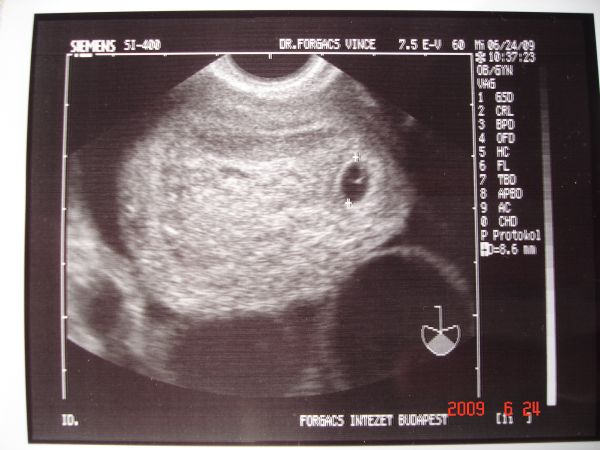

22 hetes pocaklakóval

22 hetes pocaklakóval

Szisz 24 hetesen

Szisz 24 hetesen